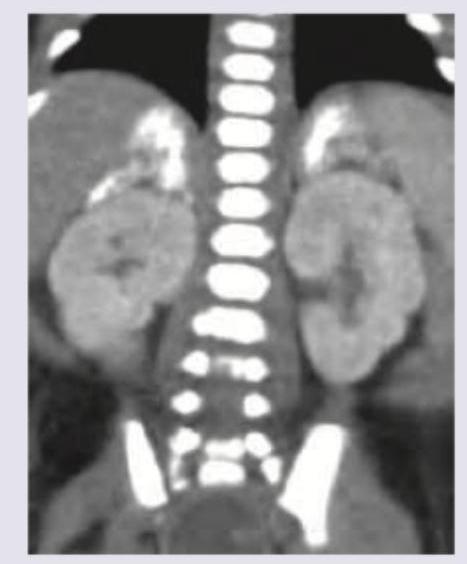

A child presents in the first week of life with recurrent vomiting, failure to thrive. On examination enlarged liver and spleen are palpated. Blood work shows hyperlipidemia and deranged LFT. CT abdomen was performed. What is the clinical diagnosis?

Explanation: ***Wolman disease*** - The constellation of **recurrent vomiting**, **failure to thrive**, **hepatosplenomegaly**, **hyperlipidemia**, **deranged LFTs** in an infant, and the presence of **adrenal calcifications** on CT abdomen (as suggested by the image showing bright areas above the kidneys) are highly characteristic of Wolman disease. - Wolman disease is a **lysosomal storage disorder** caused by a deficiency in **lysosomal acid lipase**, leading to the accumulation of cholesteryl esters and triglycerides in various tissues, particularly the liver, spleen, and adrenal glands. *Von Gierke disease* - This is a **glycogen storage disease** (Type I), characterized by **hypoglycemia**, lactic acidosis, hyperlipidemia, and hepatomegaly, but typically **without adrenal calcifications** or splenomegaly as prominent features in the first week of life. - While it causes hepatomegaly and hyperlipidemia, the profound adrenal calcification seen on CT rules it out as the primary diagnosis given the presented image. *Tay-Sachs disease* - This is a **lysosomal storage disorder** affecting hexosaminidase A, leading to GM2 ganglioside accumulation, primarily in neurons. - Clinical presentation involves **neurological deterioration**, **cherry-red spot on the retina**, and seizures, but typically **no hepatosplenomegaly, adrenal calcifications, or significant liver dysfunction**. *Biotinidase deficiency* - This is a metabolic disorder affecting biotin metabolism, presenting with **neurological symptoms** (seizures, hypotonia), skin rash, and alopecia. - It does **not typically involve hepatosplenomegaly, hyperlipidemia, or adrenal calcifications**.